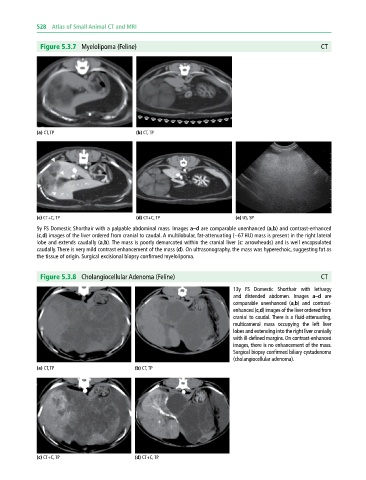

Figure 5.3.7 Myelolipoma (Feline) CT

(a) CT, TP (b) CT, TP

(c) CT+C, TP (d) CT+C, TP (e) US, SP

9y FS Domestic Shorthair with a palpable abdominal mass. Images a–d are comparable unenhanced (a,b) and contrast‐enhanced

(c,d) images of the liver ordered from cranial to caudal. A multilobular, fat‐attenuating (−67 HU) mass is present in the right lateral

lobe and extends caudally (a,b). The mass is poorly demarcated within the cranial liver (c: arrowheads) and is well encapsulated

caudally. There is very mild contrast enhancement of the mass (d). On ultrasonography, the mass was hyperechoic, suggesting fat as

the tissue of origin. Surgical excisional biopsy confirmed myelolipoma.

Figure 5.3.8 Cholangiocellular Adenoma (Feline) CT

13y FS Domestic Shorthair with lethargy

and distended abdomen. Images a–d are

comparable unenhanced (a,b) and contrast‐

enhanced (c,d) images of the liver ordered from

cranial to caudal. There is a fluid‐attenuating,

multicameral mass occupying the left liver

lobes and extending into the right liver cranially

with ill‐defined margins. On contrast‐enhanced

images, there is no enhancement of the mass.

Surgical biopsy confirmed biliary cystadenoma

(cholangiocellular adenoma).

(c) CT+C, TP (d) CT+C, TP